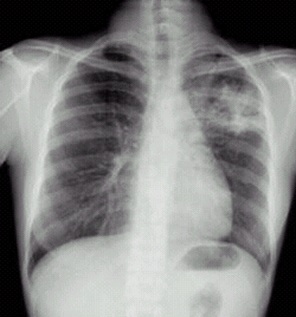

03卷-3.病史:男性,34岁,咳嗽、无痰半月,伴低热。诊断(本题满分2.00分)

A.左上支气管扩张

B.左上肺炎

C.左上浸润型肺结核

D.左侧胸腔积液

本题答案:C

题目解析:【该题针对“X线-浸润型肺结核”知识点进行考核】